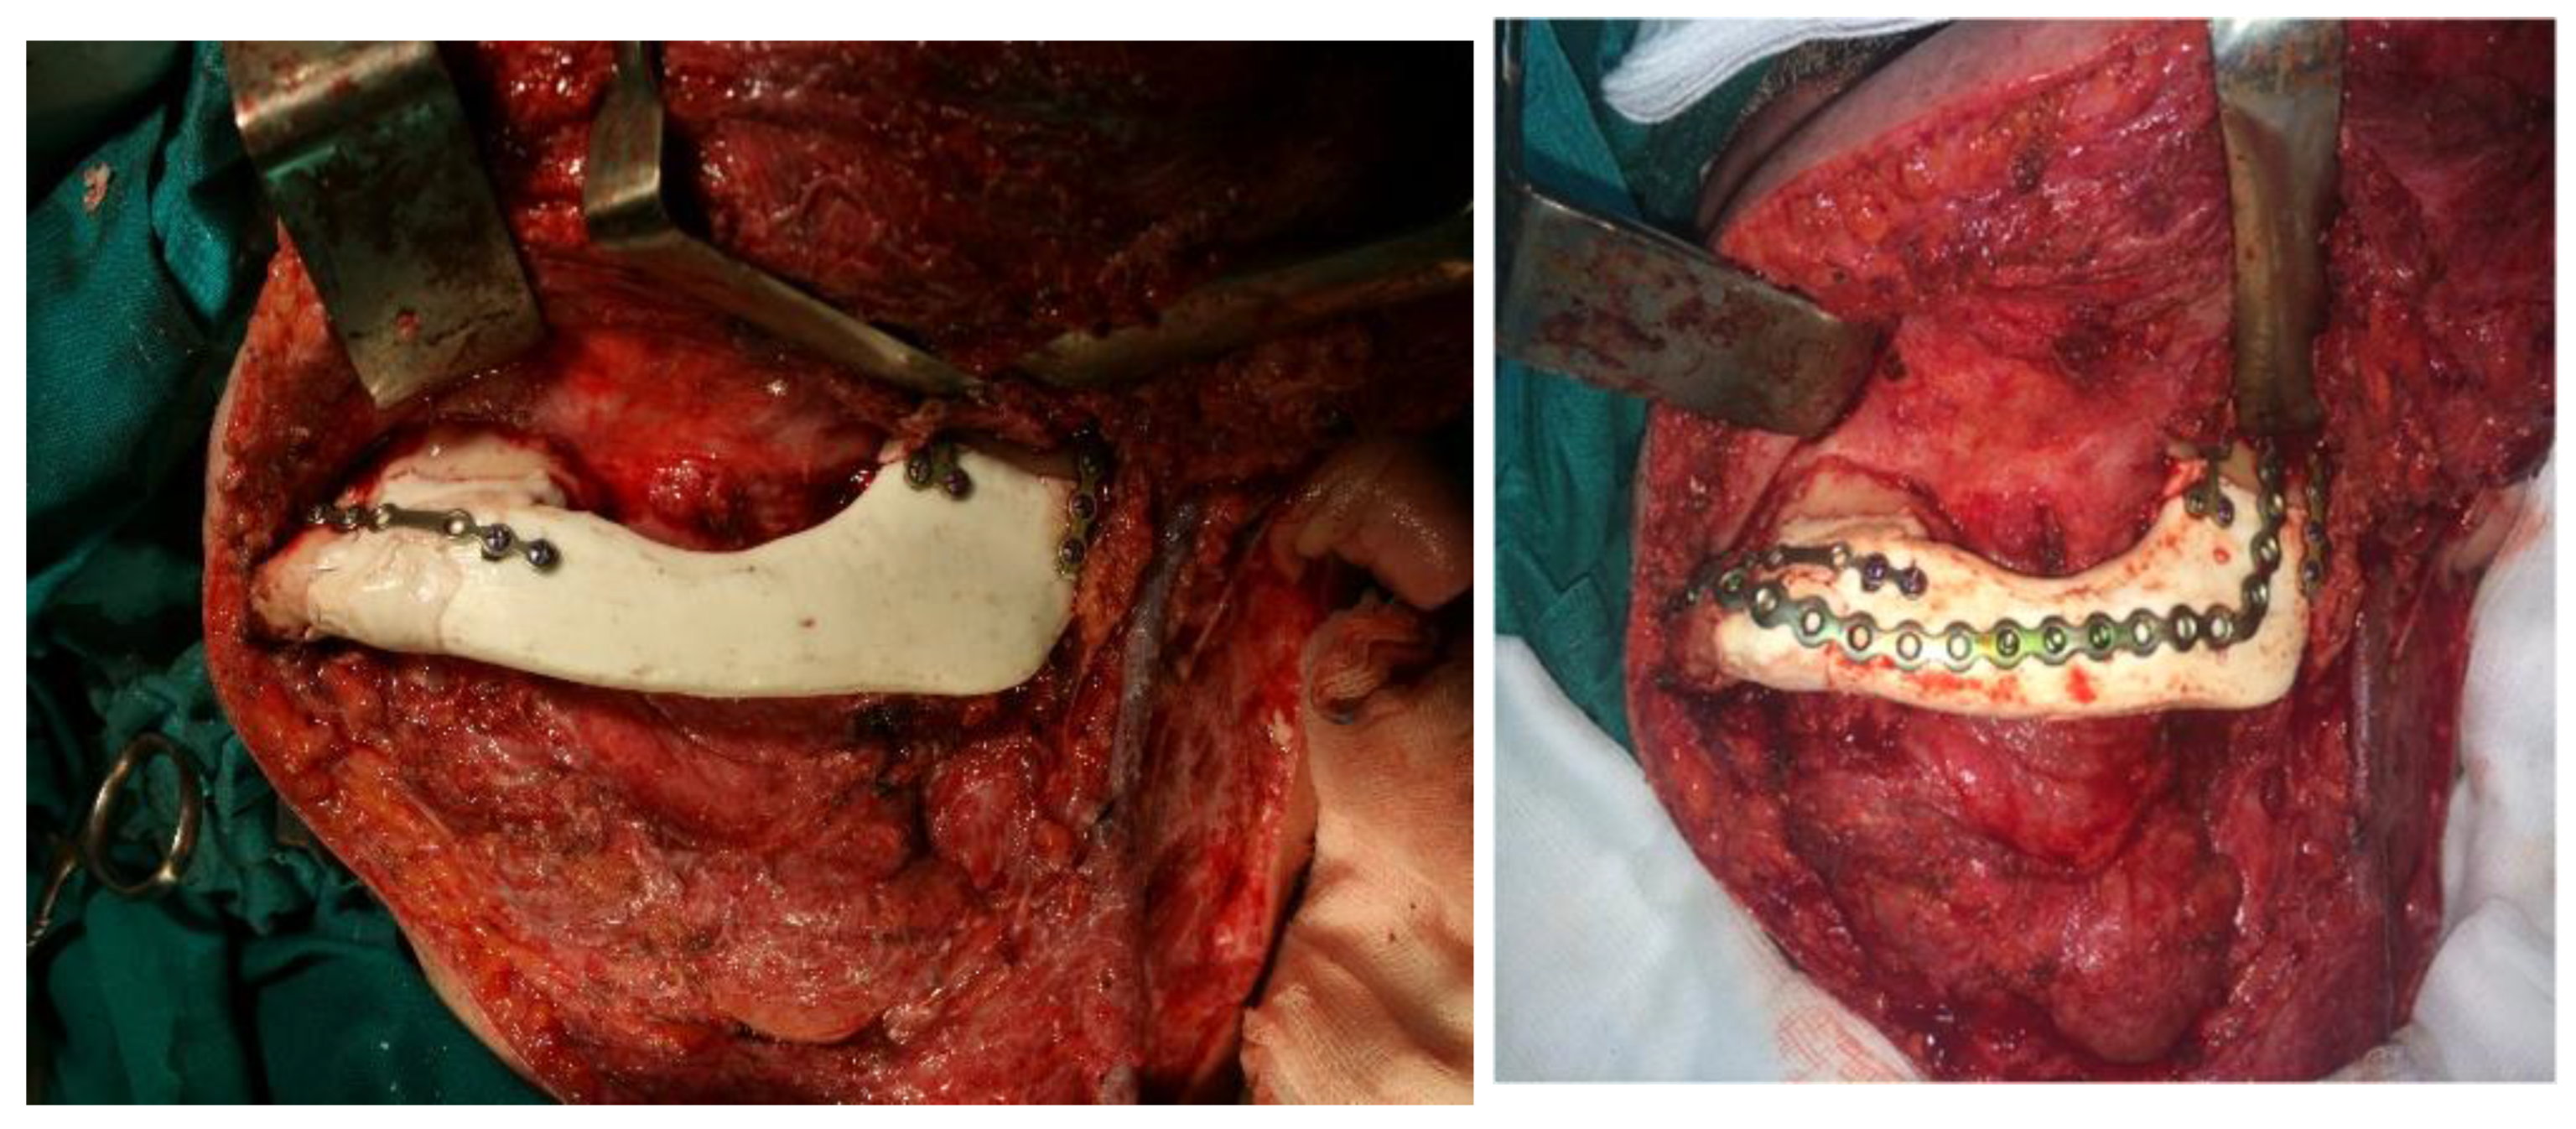

- phase 3: Computer modeling of the implant

- phase 5: Implant mold and final shape of the implant

3. Results

- phase 4: Cutting the model into the final shape of the implant